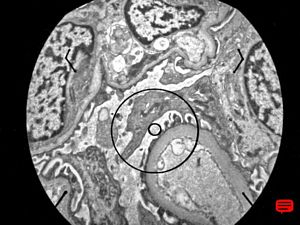

F,14y. | Alport syndrome - split and laminated, thick/thin basement membranes